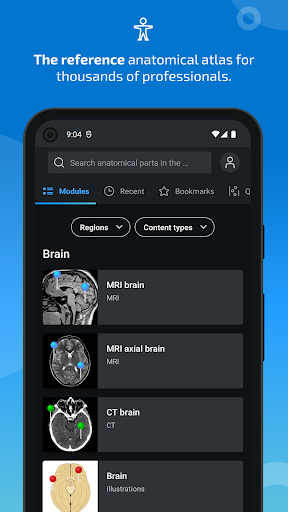

e-Anatomy memiliki lebih dari 26.000 gambar yang berisi serangkaian gambar dalam tampilan aksial, koronal, dan sagital serta radiografi, angiografi, gambar diseksi, bagan anatomi, dan ilustrasi. Semua gambar medis diberi label dengan cermat, lebih dari 967.000 label tersedia dalam 12 bahasa termasuk Terminologia Anatomica Latin.

- Gulir set gambar dengan menyeret jari Anda

- Perbesar dan perkecil

- Ketuk label untuk menampilkan struktur anatomi

- Pilih label anatomi berdasarkan kategori

- Mudah menemukan struktur anatomi berkat pencarian indeks